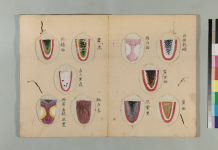

舌質正常・苔薄白・脈弦。

舌質淡・舌苔少・脈沈弱。

舌淡・脈弱無力。